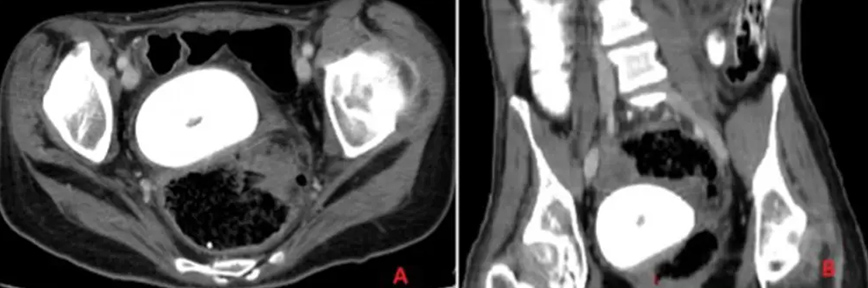

Τα συμπτώματα παρατηρήθηκαν τρεις ημέρες πριν η ασθενής μεταφερθεί εσπευσμένα στη ΜΕΘ. Είχε πυρετό, ρίγη, εμετούς, πόνους στην κοιλιά και μειωμένη όρεξη. Η αξονική τομογραφία σε λεκάνη και στην κοιλιά αποκάλυψε τον λόγο.

Το μέγεθος ήταν τόσο μεγάλο που πίεζε την ουροδόχο κύστη της γυναίκας, κάτι που οδήγησε σε ακόμη μεγαλύτερη διαρροή ούρων. Γιατροί από το Πανεπιστήμιο του Λιβάνου στη Βηρυτό διέλυσαν τον σχηματισμό της πέτρας με θεραπεία λέιζερ μέσω κρουστικών κυμάτων υπερήχων από μια συσκευή που τοποθετήθηκε στην κοιλιά της γυναίκας.